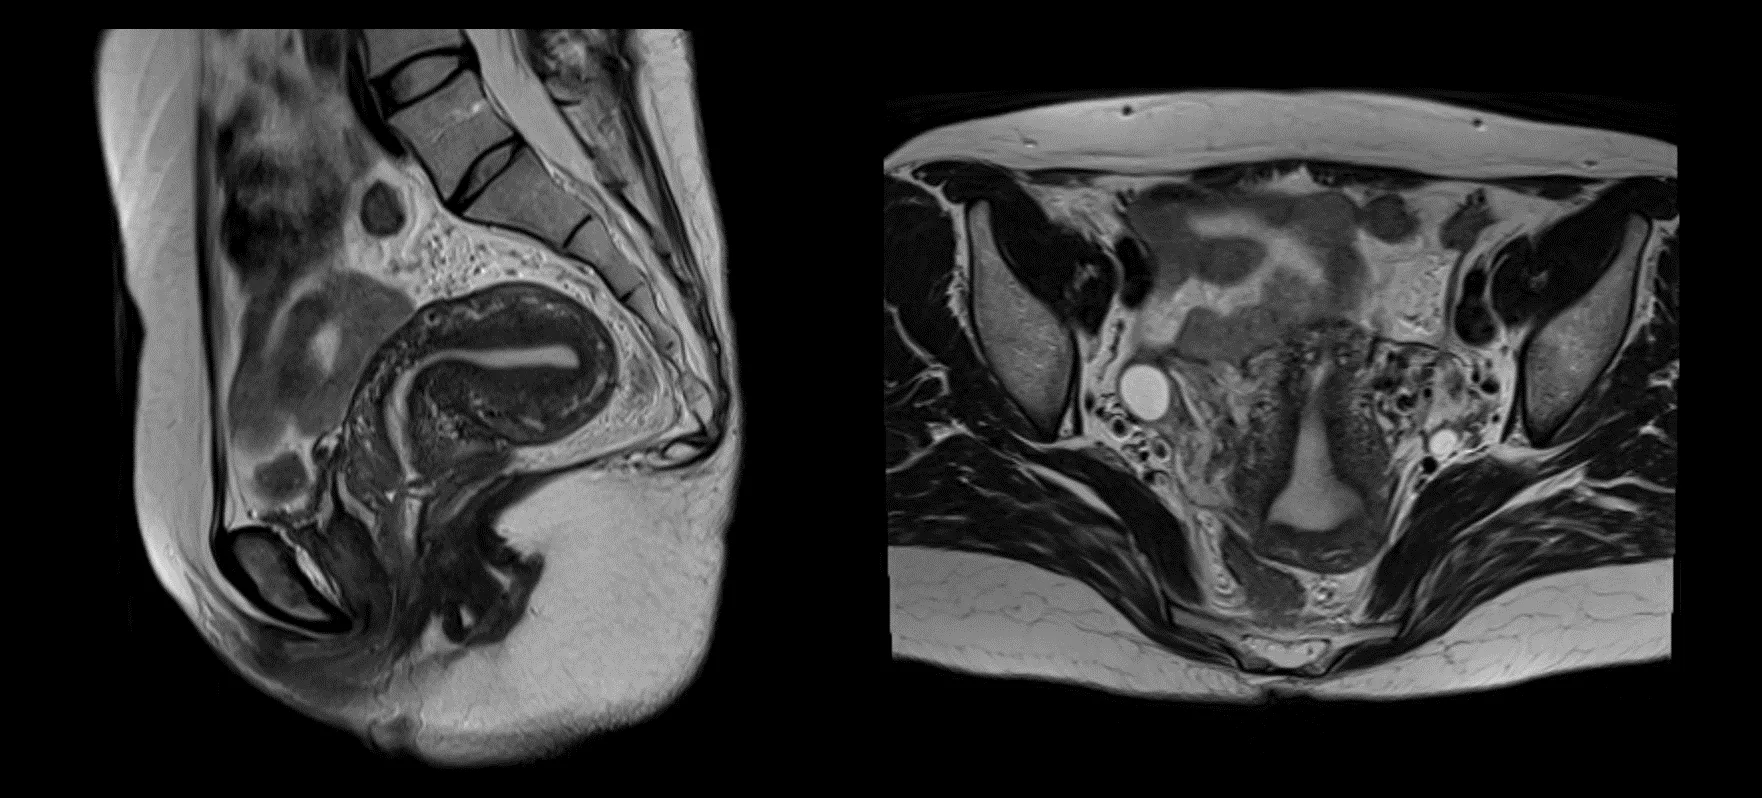

난소암을 진단하기 위한 주요 검사 방법에는 초음파 검사, CA-125 혈액 검사, CT 또는 MRI 스캔이 포함됩니다.

- CT와 MRI는 암의 진행 상태 및 전이 여부를 확인하는 데 유용합니다.